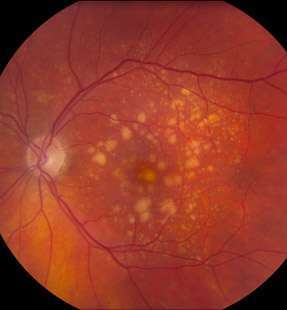

AMD is a common eye condition and a leading cause of vision loss among people age 50 and older. It causes damage to the macula, a tiny area near the center of the retina and the part of the eye responsible for sharp, central vision, which is straight ahead. In some people, AMD advances so slowly that vision loss does not occur for a long time. In others, the disease progresses quickly and may lead to a loss of vision in one or both eyes. As AMD progresses, a blurred area near the center of vision is a common symptom. Over time, the blurred area may grow larger or you may develop blank spots in your central vision.

EARLY AMD

INTERMEDIATE AMD

In neovascular AMD, also called WET AMD, abnormal blood vessels grow underneath the retina. These vessels can leak fluid and blood, which may lead to swelling and damage of the macula. The damage may be rapid and severe, unlike the more gradual course of Dry AMD. It is possible to have both DRY and WET AMD in the same eye, and either condition can appear first.